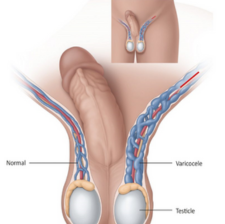

Varicocele

A varicocele (VAR-ih-koe-seel) is an enlargement of the veins within the loose bag of skin that holds the testicles (scrotum). These veins transport oxygen-depleted blood from the testicles. A varicocele occurs when blood pools in the veins rather than circulating efficiently out of the scrotum